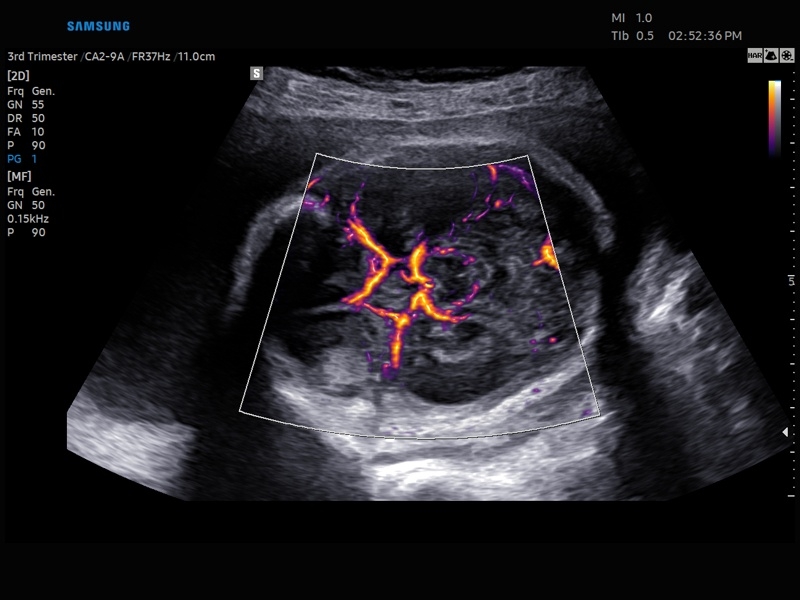

Ультразвуковой сканер V8-RUS является экспертным классом (премиальный уровень) и производится компанией Samsung Medison. Сканер V8 обеспечивает превосходное качество изображения благодаря использованию технологии Crystal Architecture™, которая включает в себя передовое аппаратное обеспечение, монокристальную технологию изготовления датчиков и сложную программную обработку ультразвуковых лучей.

Samsung Medison V8 представляет собой современную ультразвуковую систему, в которой воплощен многолетний опыт компании Samsung в создании эргономичного и интеллектуального диагностического оборудования. Система оснащена передовыми инструментами автоматизации, которые значительно упрощают рабочий процесс и повышают эффективность исследований.

Система Samsung Medison V8 обеспечивает высококачественную диагностику в различных областях медицины:

• Абдоминальные исследования

• Акушерство и гинекология

• Технологии визуализации: MV Flow, LumiFlow, SEE Stream, Panoramic

• Модуль MV-Flow – программа (режим), позволяющая визуализировать кровоток в микроциркуляторном русле с высоким разрешением без использования контраста.

• Модуль LumiFlow – программа отображения кровотока с объемной графикой для лучшего понимания архитектоники сосудистого русла.

• Модуль MV-Flow - программа (режим), позволяющая визуализировать кровоток в микроциркуляторном русле с высоким разрешением без использования контраста.